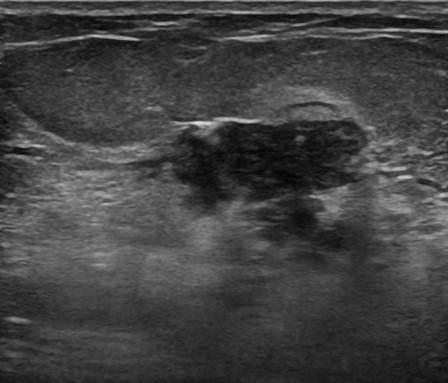

Ung thư vú

Ung thư vú - Ảnh 4

» Thông tin: Nữ giới – 58 tuổi.

» Lâm sàng: Khối tuyến vú.